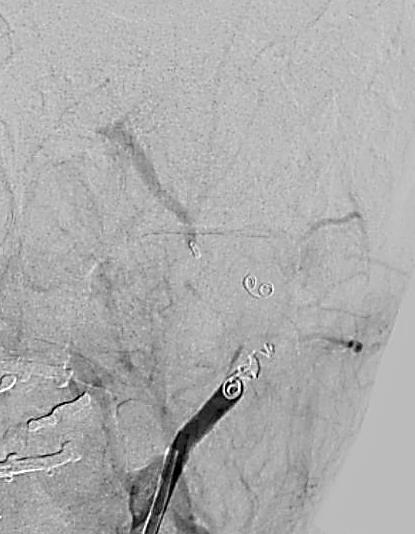

Kontrolna arteriografia potwierdziła zamknięcie naczynia, następnie nieznacznie wycofano cewnik i w ten sam sposób zamknięto światło tętnicy szyjnej zewnętrznej (ryc. 4).

Ryc. 4. Embolizacja tętnicy szyjnej zewnętrznej. Brak przepływu krwi w tętniaku.